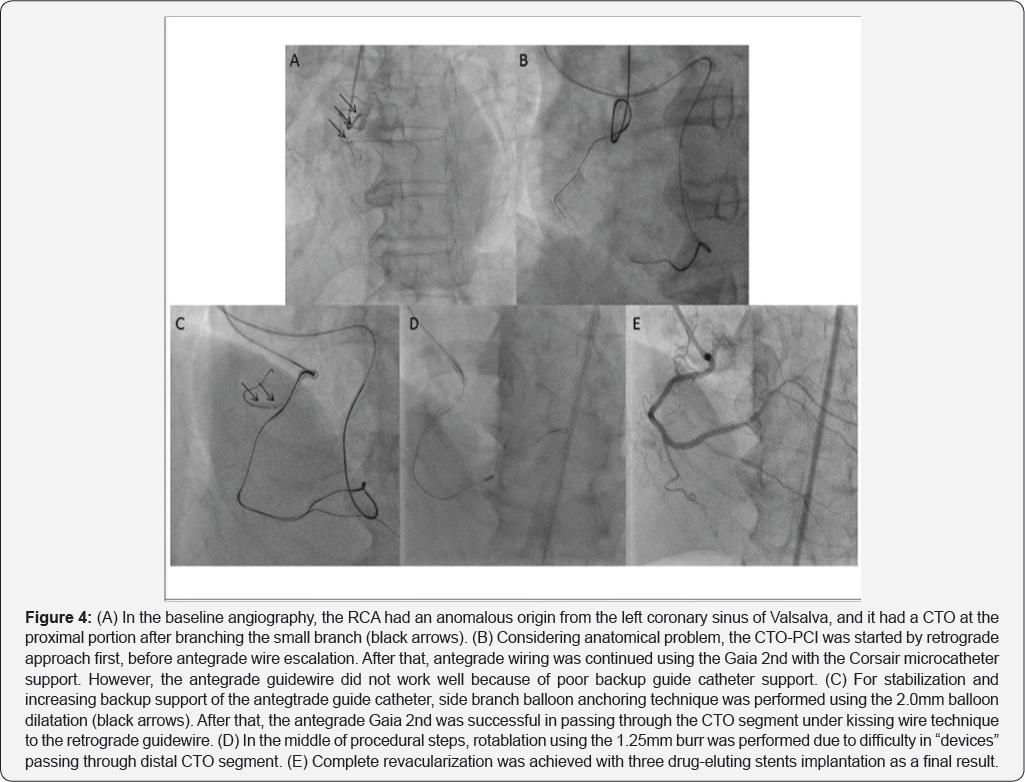

There are disadvantages of prevent selective cannulation and inadequate coaxial support of guide catheters regarding CTO-PCI to ARCA from LSOV. However, development of devices or utilization of procedural means including bilateral approach, various anchoring balloon technique, and child-in-mother technique might make possible interventional revascularization to overcome these disadvantage of anatomical condition now at last (Figure 3 & 4).